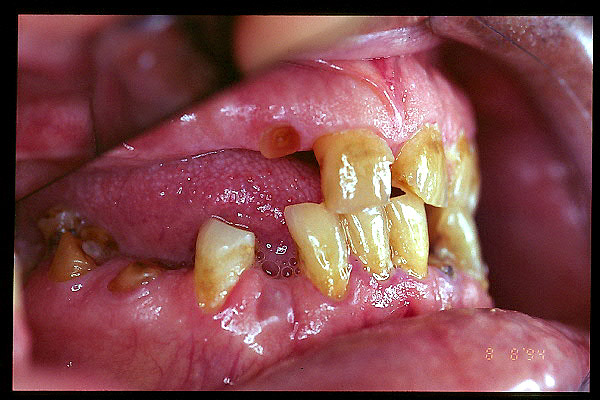

CM Enfermedad periodontal avanzada